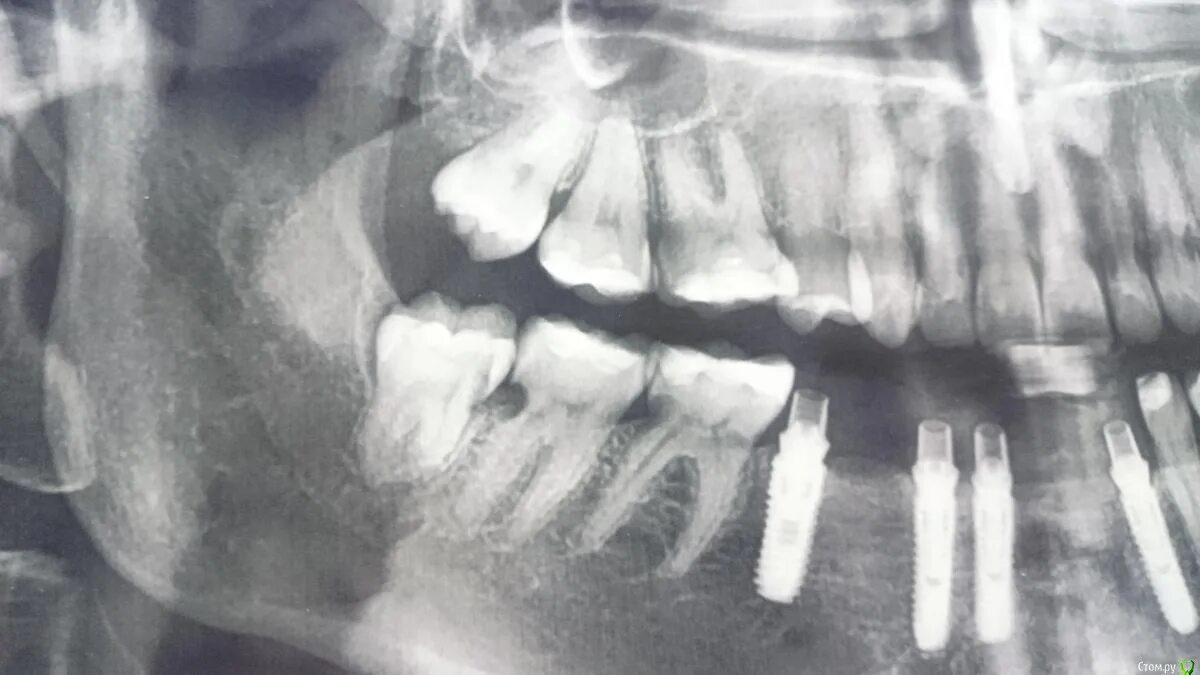

Резорбция епифанов